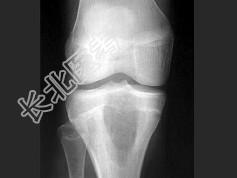

- 单项选择题女,13岁, 右膝部痛,结合图像, 最可能的诊断是 ( )

A、胫骨近端动脉瘤样骨囊肿

B、胫骨近端成软骨细胞瘤

C、胫骨近端骨巨细胞瘤

D、胫骨近端内生软骨瘤

E、以上都不是